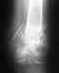

У меня был открытый перелом малой берцовой кости с разрывом синдесмоза и вывихом стопы кзади и кнаружи. Операции небыло. Месяц на вытяжке, два месяца в гипсе. Спустя еще два месяца начались боли в суставе при ходьбе. Сделал повторный ренген - незначительно разошелся синдесмоз и укоротилась малая берцовая кость. Предлагают два способа лечения:- Поставить болт-стяжку на синдесмоз.- рассечь малую берцовую кость и поставить аппарат Елизарова. Посоветуйте что делать?

Неободима болт- стяжка с диафизарной накладкой с целью восстановления взаимоотношения в г/стопном суставе